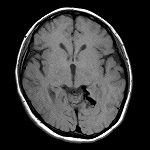

画像をクリックすると拡大表示、症例No.をクリックすると詳細ページが表示されます。本ページには2004年以降の症例のみを掲載しています。

2021年1月、Journal of Neurosurgery(米国)の手術ビデオ特集に選ばれた当院脳外科による「中小脳脚AVMの手術」(Usefulness of the middle cerebellar peduncle approach for microsurgical resection of lateral pontine AVM)は、症例No.359です。